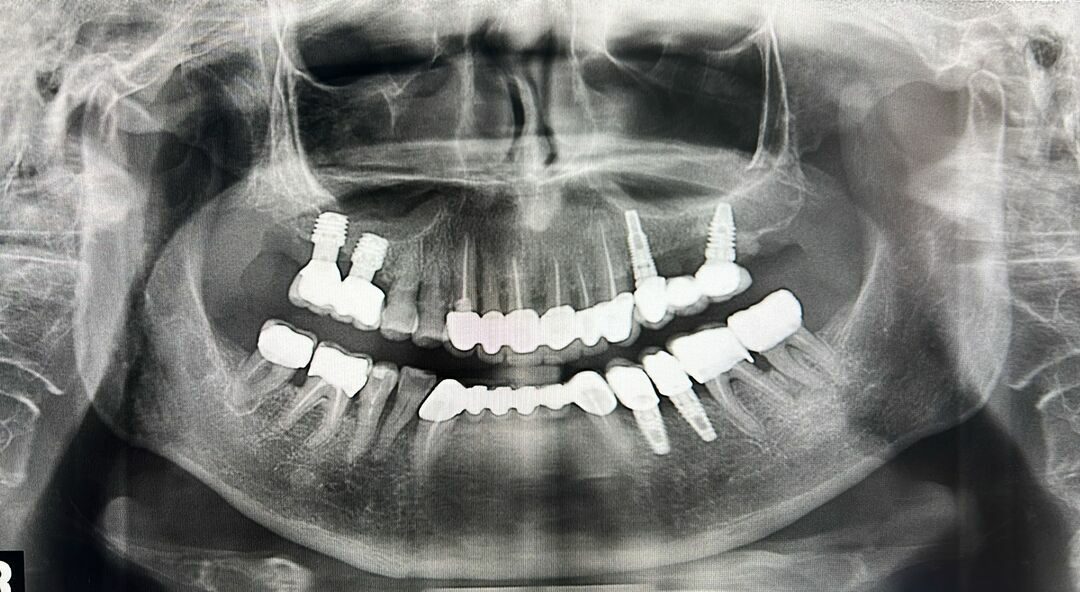

L’ortopanoramica dentale è una radiografia che mostra in un’unica immagine entrambe le arcate dentarie, la mandibola, il mascellare, le articolazioni temporo-mandibolari e parte dei seni mascellari. Rispetto alle radiografie endorali, che riprendono singoli denti, la panoramica fornisce una visione globale.

Guardando un’ortopanoramica potresti avere l’impressione di osservare una foto sfocata in bianco e nero, ma in realtà ogni parte ha un significato preciso.

Nella parte superiore si vede l’arcata mascellare, nella parte inferiore la mandibola. Ogni dente appare con la sua radice, ben ancorata all’osso. I denti sani compaiono come sagome compatte e regolari, mentre una carie dentale può mostrare zone più scure o irregolari.

Sono visibili anche le articolazioni temporo-mandibolari, che collegano la mandibola al cranio, e i seni mascellari, importanti per escludere infezioni o patologie.